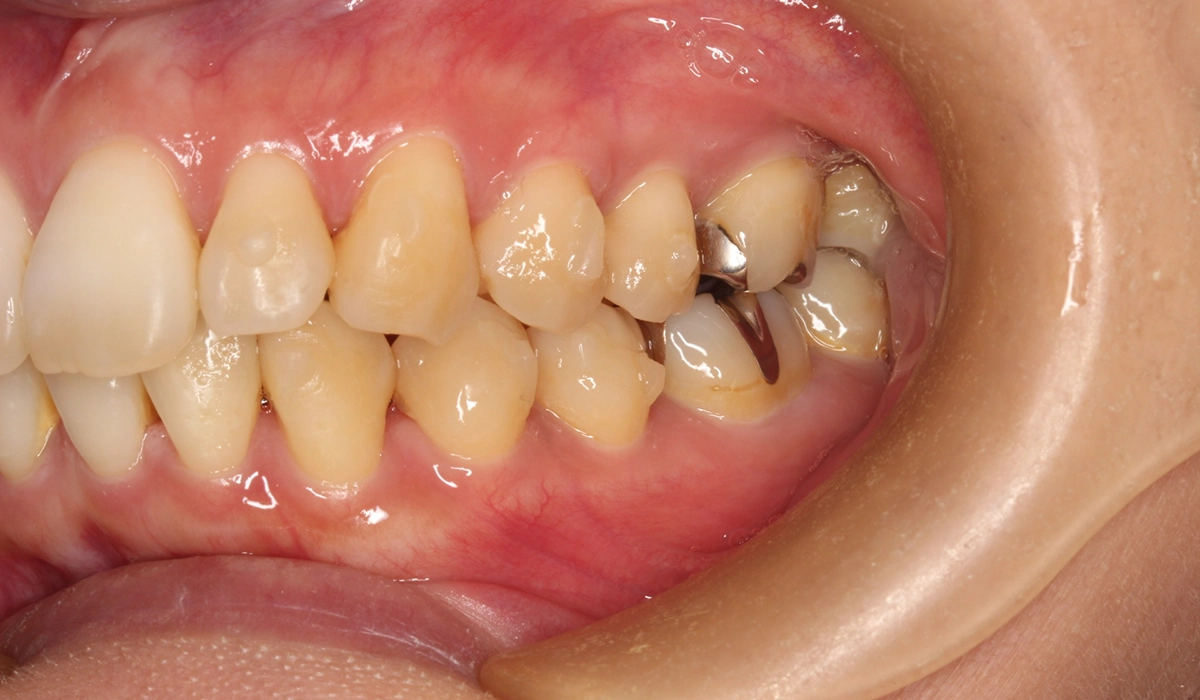

術前:左側

術後:左側